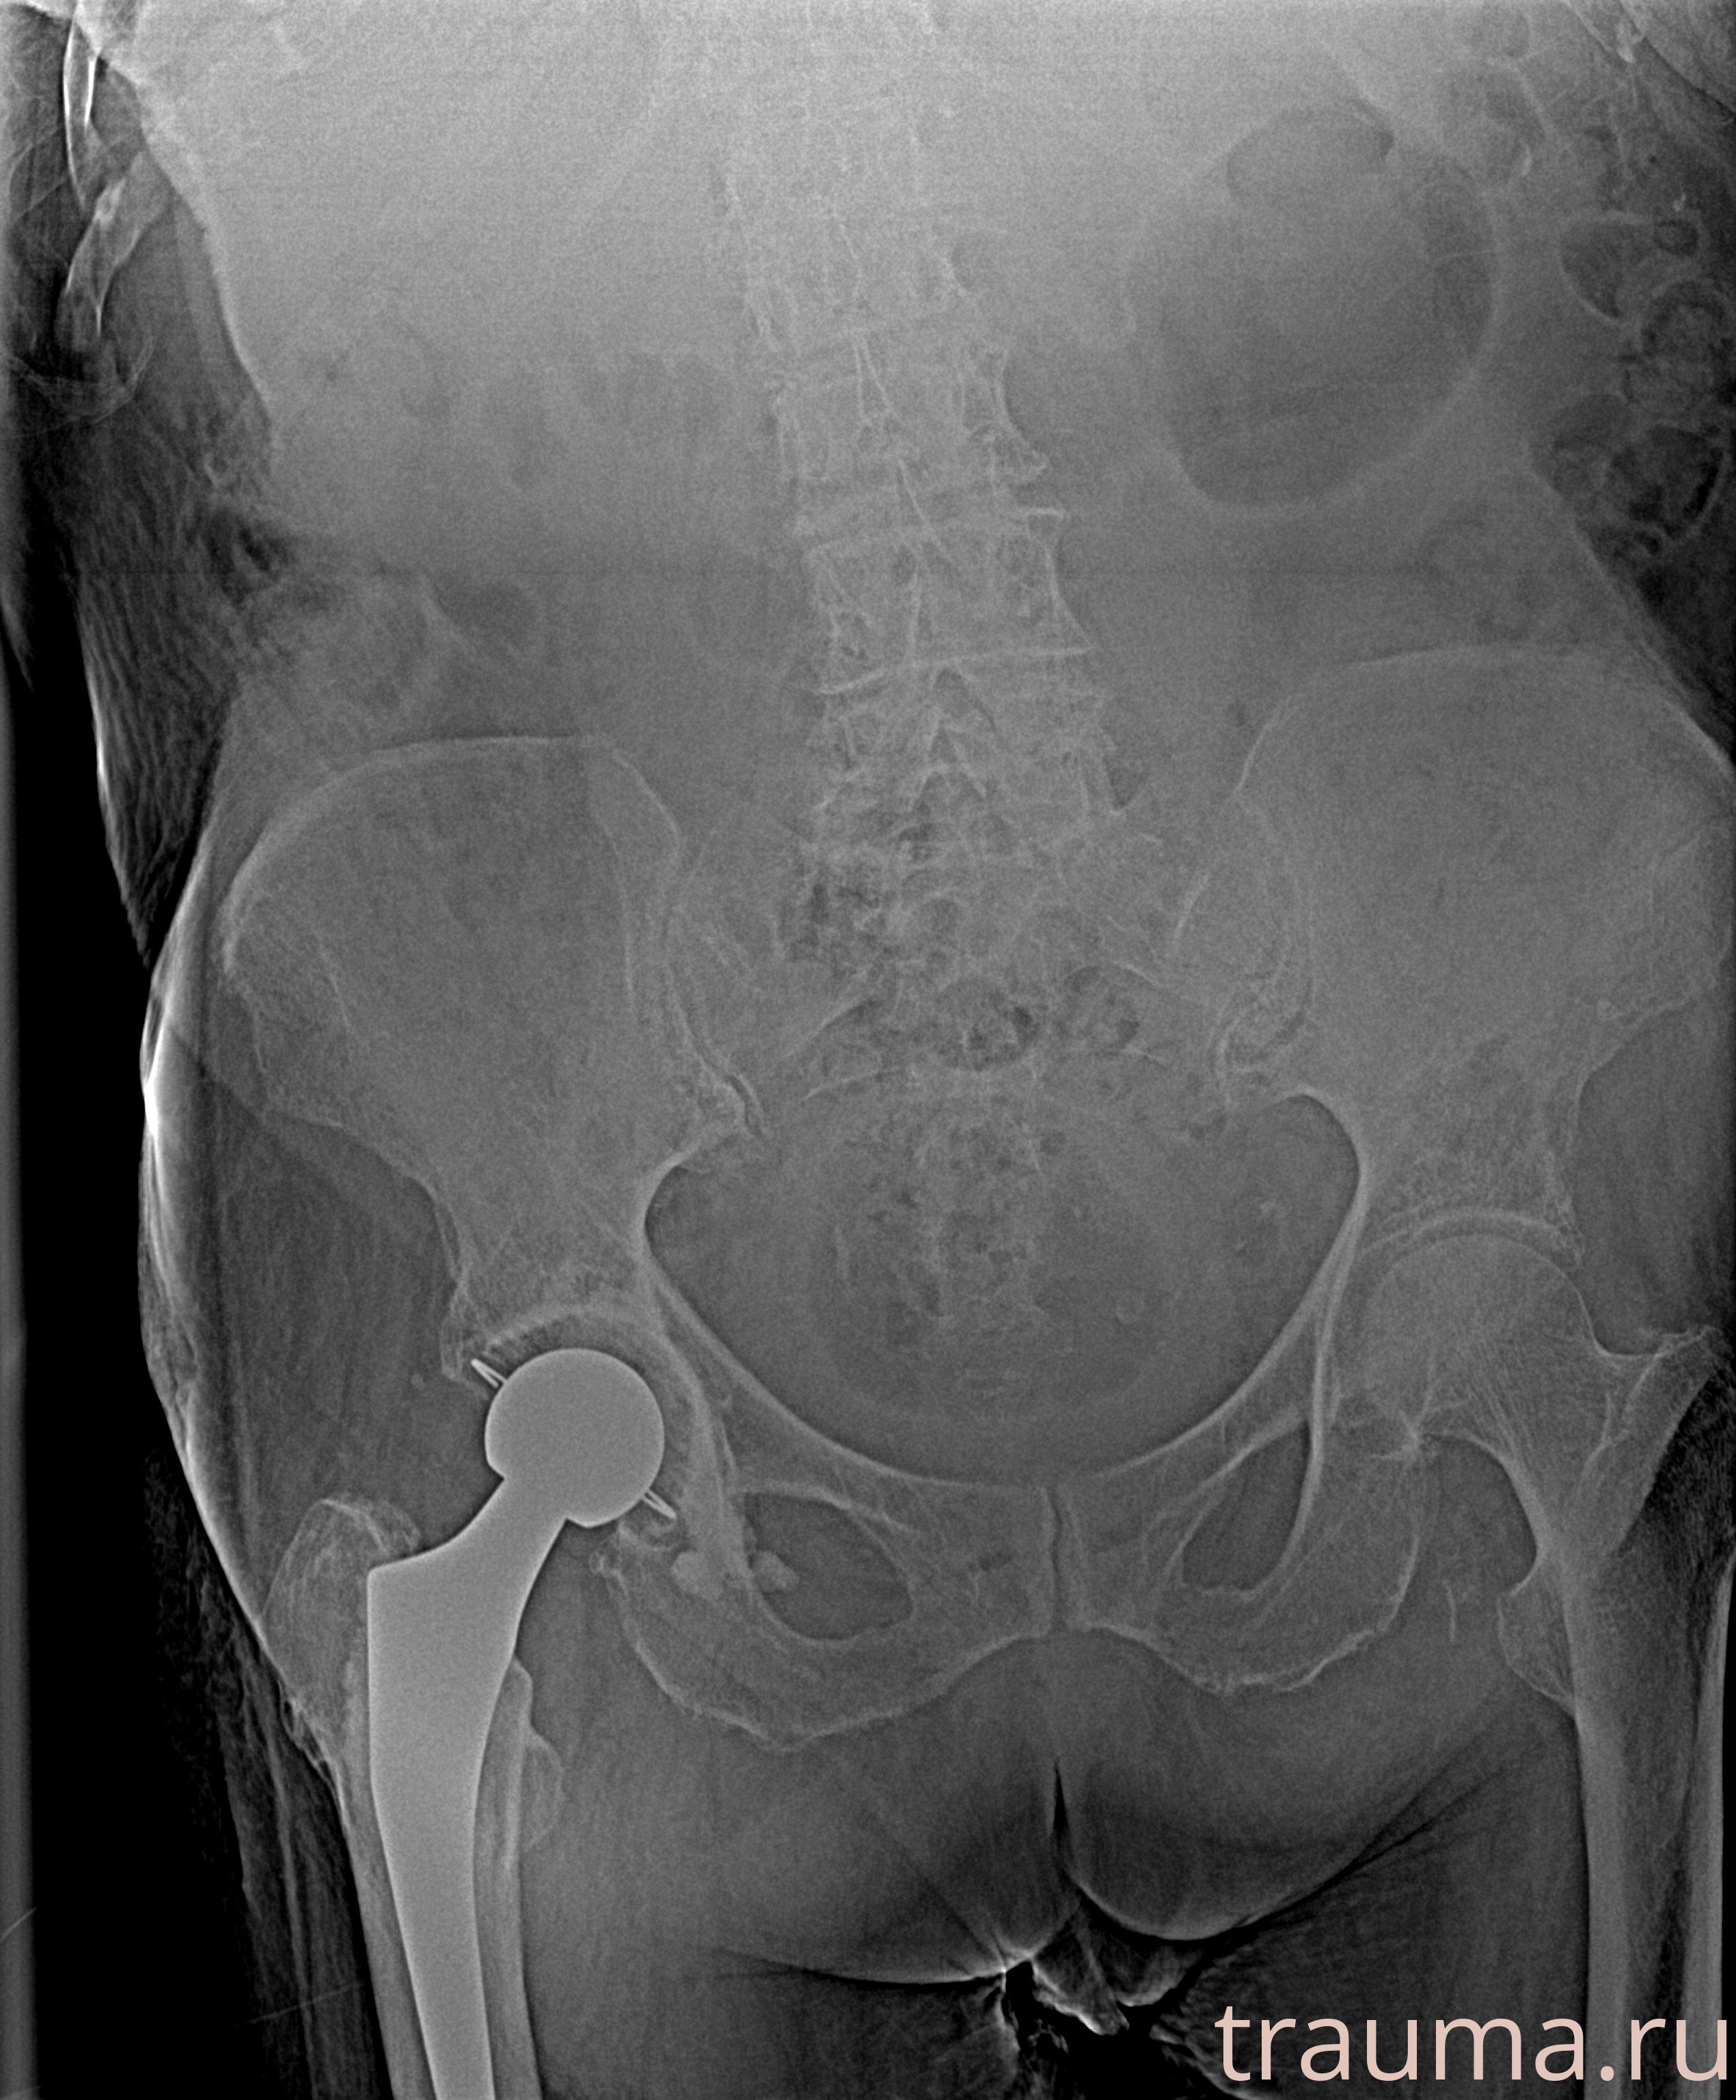

Первая помощь при переломе шейки бедра

Рентген на дому: по вашему адресу приезжает врач-рентгенолог, травматолог-ортопед с мобильным рентгеновским аппаратом, проводит диагностику травмы или заболевания, делает необходимые рентгенограммы, дает рекомендации по дальнейшему лечению. Получить качественные снимки в домашних условиях возможно благодаря уникальной методике, разработанной МосРентген Центром для института  Склифосовского